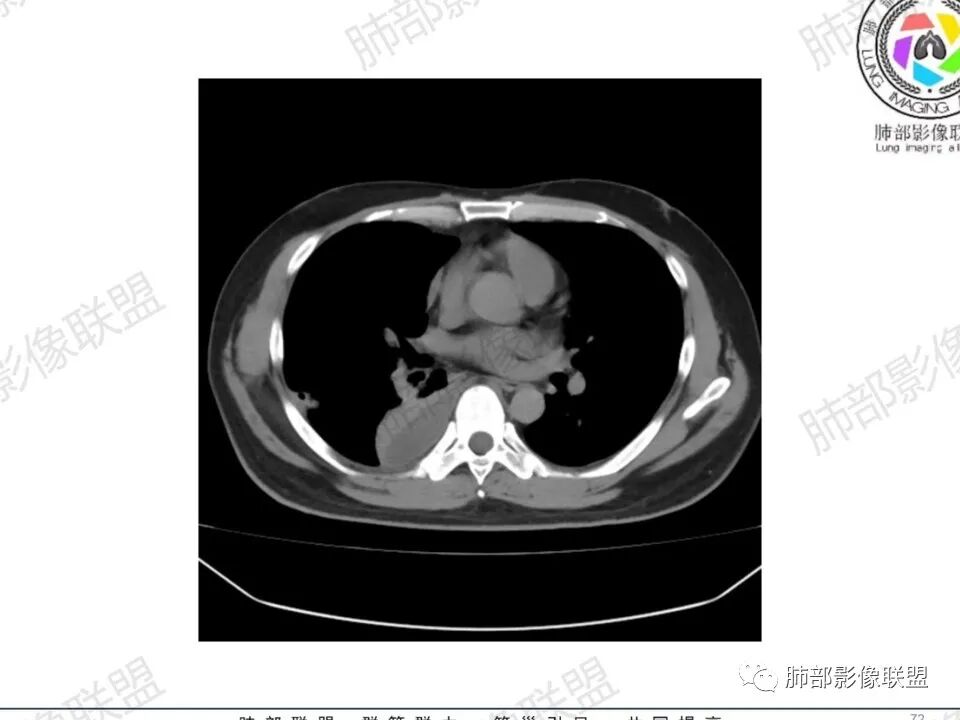

双肺多发结节,胸膜下为主,部分可见空洞。左肺上叶尖后段结节较大,分叶毛刺,周围可见长条索及小斑片影,内空洞比较光滑,内侧壁可见支气管通过。右肺下叶后基底段不张实变,后侧积液,右侧水平裂积液,右侧膈胸膜纵膈胸膜增厚积液,右侧侧胸膜肥厚,考虑1:一元金葡。2二元:金葡,左肺上叶结核。

中年男性,左手中指及胸壁疼痛伴发热来诊,影像见双肺多发结节,胸膜下分布为主,部分结节可见空洞,边缘模糊。左肺上叶尖后段结节较大。右肺下叶后基底段不张实变,右侧叶间裂及右侧胸腔积液,右侧侧胸膜肥厚。考虑金葡菌感染,血播SPE。

空洞内壁光滑,偏心厚壁空洞,张力高

胸水,部分包裹